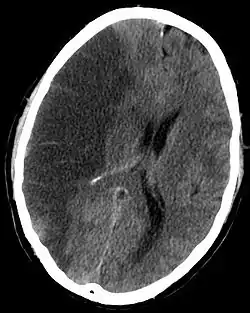

![]() صورة أشعة تظهر احتشاء الدماغ في النصف الأيسر صورة أشعة تظهر احتشاء الدماغ في النصف الأيسر | |